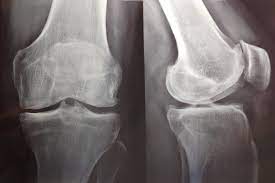

Artrosis de rodilla: eficacia y seguridad de la viscosuplementación

07 julio 2022

Existe evidencia concluyente de que la viscosuplementación conduce a una pequeña reducción en el dolor de la osteoartritis de rodilla en comparación con el placebo, que resulta menor a la diferencia mínima clínicamente importante. También hay evidencia concluyente de que la intervención se asocia con un riesgo aumentado de eventos adversos graves, por lo que se considera que estos hallazgos no respaldan su uso generalizado en el tratamiento de la artrosis de rodilla. British Medical Journal, 6 de julio de 2022.

Consumo de opiáceos entre pacientes con artrosis grave de rodilla

24 junio 2022

En este  estudio de utilización de medicamentos se encontró que entre los pacientes daneses con artrosis de rodilla grave, la prevalencia y el uso total de opioides se duplicó durante los 5 años anteriores a al reemplazo de rodilla. Además, el 10% de la población de estudio fue responsable del 90% de los opioides utilizados. Eur J Clin Pharmacol, 13 de junio de 2022

Plasma rico en plaquetas: sin eficacia en osteoartrosis de rodilla

29 noviembre 2021

En un ensayo clínico con 288 participantes con artrosis de rodilla y síntomas leves a moderados, la inyección intraarticular de plasma rico en plaquetas no fue superior al placebo en el alivio de los síntomas o los indicadores de estructura articular a los 12 meses. JAMA, 23 de noviembre de 2021.

Elección del calzado para la artrosis de rodilla

12 enero 2021

Contrariamente a la hipótesis de los investigadores, los zapatos con soporte estable mejoraron el dolor de rodilla al caminar más que los zapatos planos flexibles. Annals of Internal Medicine, 12 de enero de 2021.